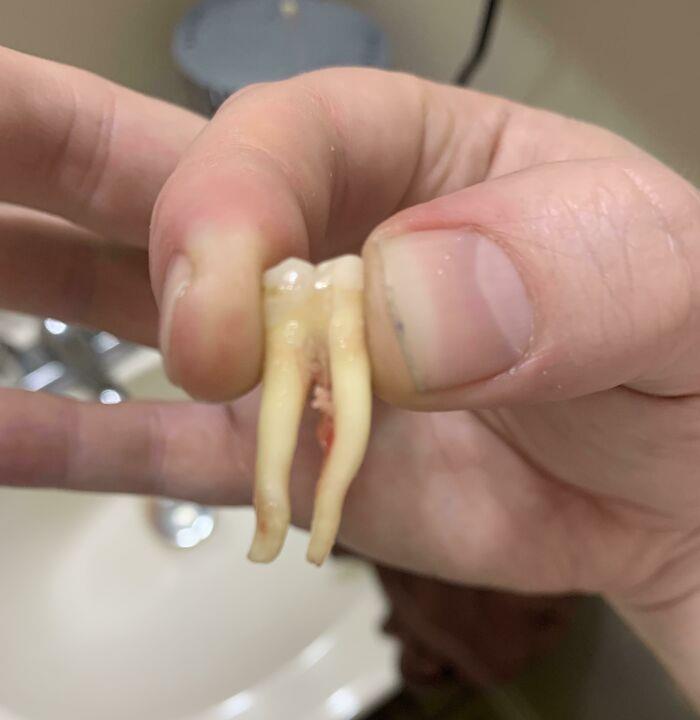

Extracted Tooth With Intact Nerve Root

My Tooth Has Really Long Roots